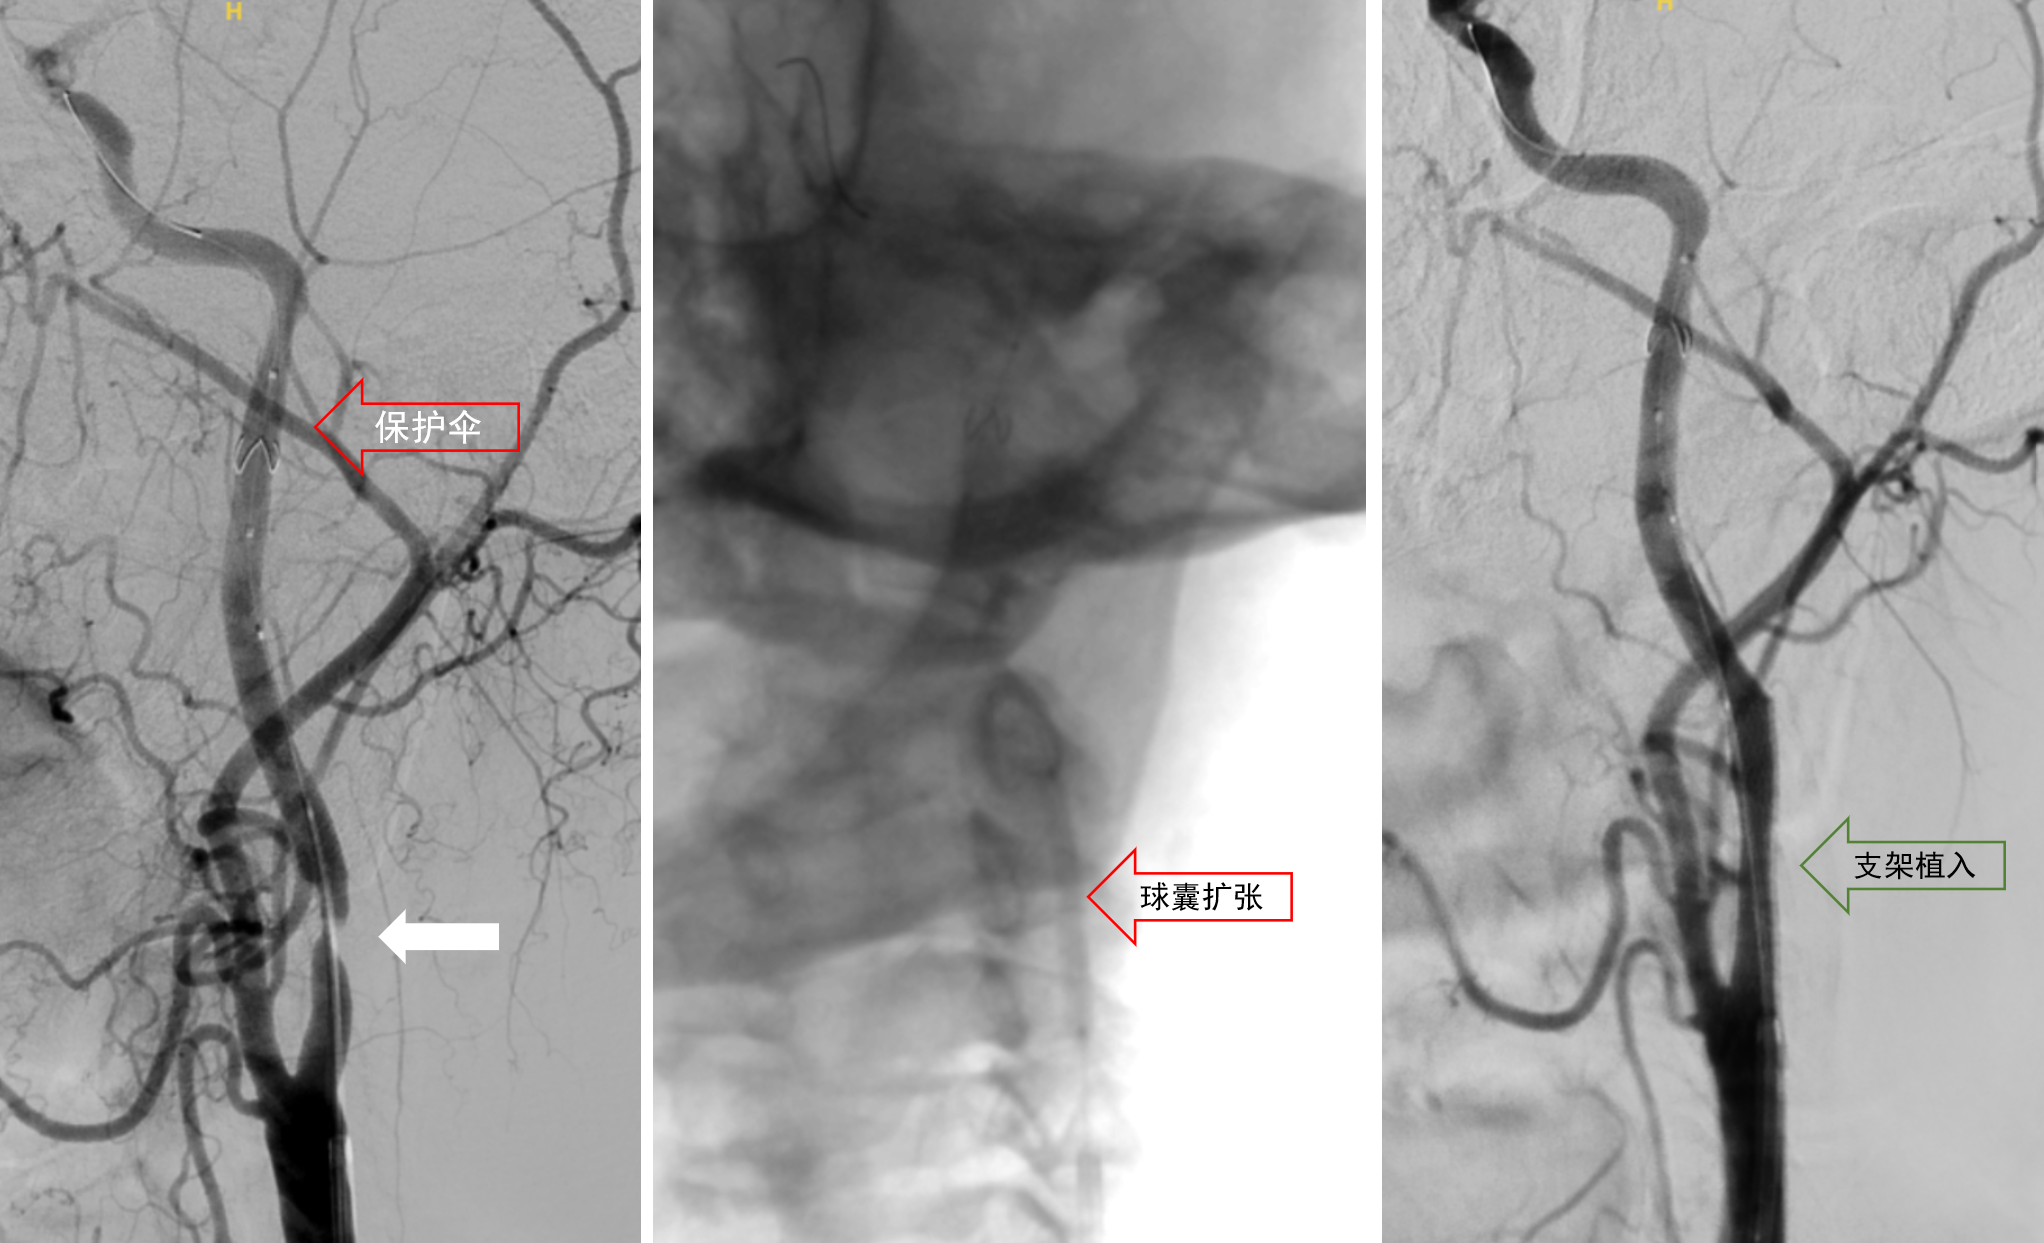

在保护伞远端拦截栓子作用下,顺利对狭窄病变进行扩张打开及支架植入手术,顺利为患者解除病变,复测OCT可见支架打开良好,部分软质斑块脱垂但成功被支架小梁支撑开通